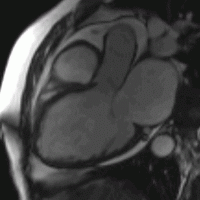

Thank you for your interest in cardiovascular imaging at the University of Wisconsin School of Medicine and Public Health, Department of Radiology. The Cardiovascular Imaging Section has long provided innovative, advanced clinical care in non-invasive cardiovascular imaging, including cardiac magnetic resonance imaging (MRI), magnetic resonance angiography (MRA), cardiac and coronary computed tomography (CCTA), and computed tomography angiography (CTA).

The volume of clinical studies has grown continuously and we now perform over 5000 non-invasive cardiovascular CT and MR studies each year. The members of our section are very active and renowned locally, nationally, and internationally with over 550 peer-reviewed publications, 30 book chapters, 1200 scientific presentations, and 50 patents. Time-resolved contrast-enhanced MRA (TRICKs), pulmonary MRA for pulmonary embolism, non-contrast-enhanced MRA, four-dimensional (4D) flow MRI, low-dose CTA and CCTA, and 3D printing are just a few examples of the innovations developed by our group that have had a significant impact on clinical care locally and beyond.